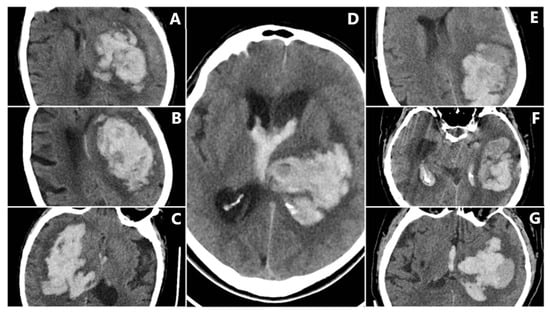

Irregular Shape (IRS) has a clearly lobulated or spiculated hematoma margin, interpreted as multifocal bleeding sources (IRS = 1 if irregular, otherwise 0) (Figure 3) [11].

Figure 3. Irregular Shape sign—three examples from our cohort.

The Satellite Sign (SS) was identified when a small (≤10 mm) hyperdense hemorrhagic focus lay within 20 mm of, but separate from, the main clot on at least one CT slice (SS = 1 if present, otherwise 0) (Figure 4) [12].

Figure 4. Satellite Sign (SS)—three examples from our cohort.